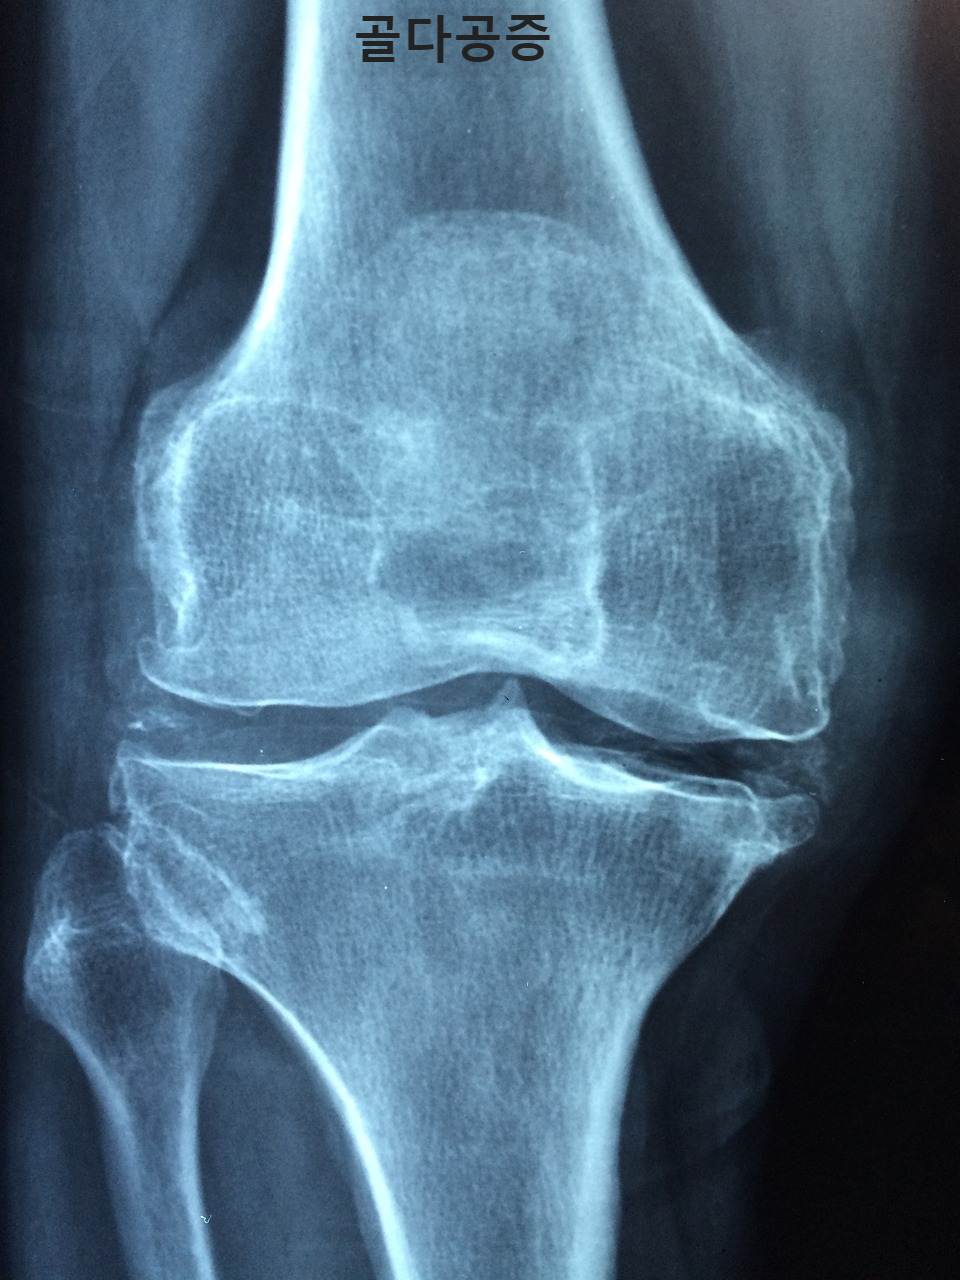

골다공증은 "구멍이 많은 뼈"로 번역되며, 정확히 이 상태에서 발생합니다. 뼈는 골밀도와 질의 감소로 인해 부서지기 쉽고 부서지기 쉽습니다. 이는 특히 엉덩이, 척추, 손목과 같은 부위에 골절의 위험이 증가하는 결과를 초래합니다. 골다공증의 기본을 이해하는 것은 필수적입니다.

일반적인 골절 부위: 척추, 고관절, 손목은 골다공증 골절에 특히 취약합니다. 척추뼈의 압박 골절은 구부린 자세와 키의 상실을 초래할 수 있습니다.